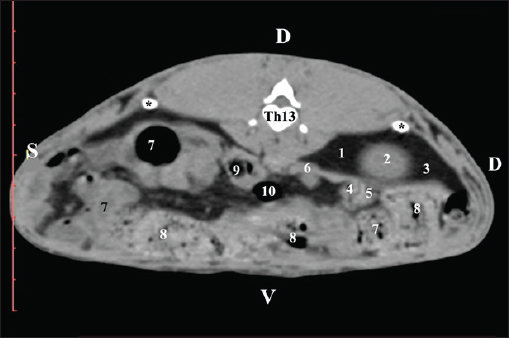

AbstractBackground: The rabbit kidney is a unipapillary organ. According to other researchers, rabbit kidneys have 6–8 pyramids. The crista renalis is well differentiated. Aim: This study aimed to describe the computed tomography (CT) anatomy and dimensions of rabbit kidneys. Methods: Ten sexually mature, clinically healthy rabbits were divided into two groups (five males and five females). The animals were positioned in the sternal position. A SOMATOM helical computed tomograph was used in the study with consecutive Dicom Viewer reconstructions of the data. Results: On transverse precontrast CT scans, the right kidney was observed between Th13 (L1) and L2–L3, and the left kidney appeared between L2 (L3) and L4 (L5). The CT value of the right kidney was 40.28 ± 6.6 HU, and that of the left kidney was 43.36 ± 5.2 HU. The CT method was precise and found an excellent positive correlation between both kidney length (Y variable) and L2 length (X variable). The Pearson correlation coefficient was 0.957 for the right kidney and 0.961 for the left kidney at 95% confidence interval. The measured length of both kidneys on CT scans demonstrated a very strong positive correlation with L2 length. Retrospective reconstruction revealed both kidneys as multipapillary organs. The cortex renis and medulla renis were sharply distinct, and the boundary between the capsula fibrosa and capsula adiposa was defined. Conclusion: The obtained in vivo results are precise and serve as an anatomical model for the use of CT in rabbits and other animal species, including humans. Keywords: Anatomy, CT, Kidney, Rabbit. IntroductionThe kidneys of rabbits are paired organs located just below the dorsal abdominal wall muscles. The position of the right kidney is asymmetrical due to the compression of adjacent organs during the embryonic period. Thus, the right kidney is placed cranially to the left one. The organs are brownish, with a specific bean-like shape, surrounded by a fibrous capsule, medially connected with the ureter, and lie retroperitoneally. The kidneys have a single papilla, and the renal pelvis is not separated. Every kidney possesses an adipose capsule, known as the capsula adiposа. After incision, the renal pelvis may be identified by the funnel-shaped expansion of the ureter’s end corresponding to the borders of the renal sinus. The renal cortex is a distinct, narrow peripheral zone. The renal medulla, including the renal papilla, forms the central part of the kidney. The renal collumnae radiate through the core (Bensley, 1948; Farhana and Wibowo, 2019). The kidneys of rabbits can be easily identified by palpation. They are highly motile. The right kidney is an intrathoracic abdominal organ (Harcourt-Brown, 2002 ). According to Brewer (2006); Vella and Donnelly (2012) and Dyce et al. (2010) the structure of the rabbit kidney is primitive compared with that of other domestic mammals. It comprises a well-defined capsule, cortex, and medulla. It is smooth and unipapillary, with only a single calyx opening directly into the ureter. The right kidney is located cranially to the left kidney. Some authors (Dimitrov and Chaprazov, 2012a,b) have described the bean-shaped and dorsoventrally flattened kidneys of rabbits. The kidneys have a well-developed cortex, medulla, renal papilla, and renal pelvis. They are bipyramidal, with a renal papilla projecting onto the hilus renalis. The rabbit kidney is similar to that of small ruminants and dogs. It comprises the cortex renis and medulla renis. The hilus renalis is strongly narrowed and adjacent to the extremitas cranialis. As in small ruminants and dogs, both kidneys have 6–8 pyramids, whose margins are poorly distinct. The cista renalis are well defined. The extremitas cranialis of the right kidney attains the 13th rib, and the extremitas caudalis attains L3. The extremitas cranialis of the left kidney is positioned within L3–L4, and the extremitas caudalis reaches L5 (Barone, 2020). A case of smooth-surface multipyramidal kidneys in a rabbit has been described (Stamatova-Yovcheva et al., 2022). The cortex and medulla were constructed using pyramid-shaped lobes. The apex of the lobes formed papillae, which protruded into the renal sinus calyces. The renal pelvis was concave. Other literature sources on the topography of rabbit kidneys (Barone, 2001; Hristov et al., 2006) describe them in the retroperitoneal space—spatium retroperitoneale; the right one being between the 11th/12th intercostal space and L2. The cranial pole of the organ is in anatomical contact with the liver, just beneath the last intercostal space. The right kidney’s caudal pole extends up to the duodenal pars descendens. The left kidney is placed ventrocaudally in relation to the right one, between L2 and L4. The jejunal loops are located ventrally to the left kidney, whereas the descending part of the sigmoid colon and corpus pancreatis are located ventrally (Barone, 2001; Hristov et al., 2006). The right kidney of rabbits is cranially located in relation to the left one, opposite to humans, where the left kidney is dorsally positioned in relation to the right one. This is due to the specific position of the liver, which occupies a considerable space to the left of the median plane and above the left kidney (Farhana and Wibowo, 2019). The right rabbit kidney lies between Th13 and L2, whereas the right kidney is located caudally and is located between L3 and L5. Margo lateralis does not contact the abdominal wall. The cranial pole of the right kidney extends up to the beginning of Th13 and contacts the liver’s lobus caudatus. The caudal pole of the right kidney reaches the end of L2; the organ is observed in the middle of the vertebral column–right abdominal wall distance. The left kidney is located laterally to the middle of the distance between the vertebral column and the left abdominal wall (Dimitrov and Chaprazov, 2012a,b). The rabbit is an experimental model of kidney transplantation in humans and for monitoring the effect of immunosuppressive drugs during the post-transplantation period (Wu et al., 2003; Saeed et al., 2020). Rabbits are prone to pyelonephritis and renal infarctions accompanied by hemorrhages. The urine is alkaline, dark yellow to brown, and contains substantial amounts of calcium carbonate and triple phosphate crystals (ammonium magnesium phosphate and calcium carbonate monohydrate) (Percy and Barthold, 2007; Harcourt-Brown, 2013). Computed tomography (CT) is a contemporary, intravital, prompt, and accurate imaging method for visualizing the kidneys and renal blood supply in mini-pigs and rabbits. The average volume of the right kidney in mini-pigs is greater than that of the contralateral kidney (Yoon et al., 2010; El-Ghazali et al., 2021). Pre-contrast CT examination of abdominal organs is a convenient method for obtaining anatomical information in small domestic mammals. The contrast examination is mainly used to define the morphology of specific parenchymal structures and vessels (Kleiter et al., 1999; Gielen et al., 2003). The pre-contrast CT examination is a reliable and precise modern method for visualizing the renal parenchyma, renal pelvis, adipose capsule, and peripelvic adipose tissue, as well as for detailed visualization of kidney calculi (Yewon et al., 2023). Compared with other imaging methods, CT is the method of choice for the exploration of the rabbit’s abdominal cavity. Both transverse and dorsal CT scans of rabbit kidneys depict the bilateral position of the organs in the regio abdominis lateralis dextra et sinistra. On consecutive transverse scans, the right kidney appears cranial to the left one. The right kidney and lobus caudatus possess comparable soft tissue density characteristics, with the hypoattenuated adipose capsule between. On the gray scale, the attenuation of the organ is medium, with gray shades. There is no difference between the density of the cortex renis and medulla renis (El-Ghazali et al., 2021). The pre-contrast CT examination of canine kidneys depicts the organs as normoattenuated homogeneous soft tissue findings. On pre-contrast scans, the crista renalis is a hyperattenuated structure compared with the relatively hypoattenuated medulla renis (Serra-Gomez de la Serna et al., 2024). An intravital CT examination of the kidneys of dogs and cats was performed to provide numerical values about the density of the cortex renis and medulla renis (Oliveira et al., 2013). The cortex of both kidneys had a greater density than the medulla. The volumes of both kidneys obtained from intravital CT imaging in dogs are proportional to the length and body weight of the studied organs. This correlation is essential for normal renal function, and deviations are considered an indication of several renal illnesses (Yewon et al., 2022). The proximity between the right kidney and the liver is clearly visible on sagittal computed tomography scans. Impressio renalis is an anatomical contact marker between the two organs, which is identified on transverse CT scans as a soft tissue hypoattenuated finding at the 13th thoracic vertebra (T13) level (Stamatova-Yovcheva et al., 2012; Stamatova-Yovcheva et al., 2013). Anatomical contact between the right kidney and proc. caudatus in chinchillas is observed at the Th13 level. The right kidney is visualized as a hyperattenuated soft tissue finding against the hypoattenuated liver (Dilek et al., 2024). Relationships exist between the length of both kidneys in dogs and the length of the second lumbar vertebra (L2); according to the findings, the body weight of biological subjects had no effect on this correlation (Hoey et al., 2016). Some authors (Atalar et al., 2017) have provided information on the macrodimensions (length and width) of the kidneys in Kangal dogs. The right kidney demonstrated greater values than the left kidney. The 3D reconstructions proved to be a reliable method for investigating the anatomical features of the kidneys, depending on the canine breed. The use of the rabbit kidney as an anatomical model in medical research, the susceptibility of the organ to species-specific diseases, and the contradictory anatomical theories about the lobulation of the organ were the main motivations for the present research. Materials and MethodsTen clinically healthy, sexually mature, 7-month-old New Zealand White rabbits weighing 2.5–3.0 kg (5 male and 5 female) were studied. A helical computed tomograph (SOMATOM) (go SN 168190 (Siemens Healthineers, Forchheim, Germany) was used in the study. The animals were in sternal recumbency. Anesthesia was applied at 15 mg/kg Zoletil® 50 IM (tiletamine hydrochloride 125 mg and zolazepam hydrochloride 125 mg in 5 ml of solution) (Virbac, Carros-Cedex, France). It was administered intramuscularly to the gluteal muscles. The animals were studied in the Radiology Unit of Trakia University, Faculty of Veterinary Medicine hospital. The abdominal cavity was investigated from the regio abdominis cranialis to the appertura pelvis cranialis. Twenty slices were obtained from each rabbit. The scanning parameters were as follows: the thickness of the slices was 0.7 mm, the electric current intensity was 30 mA, the collimation thickness was 16 × 0.75 mm, the X-ray tube current was 250 mA, the scanning time was from 0.8 to 1.0 seconds for each slice, the CT dose index volume was 55.10, and mGy was 10. The matrix was 1024 pixel matrix high-resolution CT, the rotation time was up to 0.5 seconds, the rotational speed was 360° in 0.8, 1, 2, 3, and 4 seconds; the pitch was 6, the anode tension was 130 kV, the zoom was 145%, the window level was 50, the window width was 350, the exposure time was 1981 s, CTDIvol was 1.67 mGy, the converting filter was standard, the tilt was 0.5, the level was 35, and the Field of view (FOV) was 50. Transversal slices were obtained between the planes from the Th13 thoracic vertebra to the L5 lumbar vertebra. Images were visualized using the RadiAnt Dicom Viewer (2025.1 BETA 64-bit). Retrospective reconstructions were obtained using the Angio–Right and Left, MIP B/W, Bones and Skin 1, and Bones and Skin 3 algorithms through the RadiAnt Dicom Viewer software. Soft tissue density data were statistically processed. A radiological specialist regularly calibrated the system. A gating system was used to obtain high-resolution slices. The pre-contrast CT study was conducted to study the topography of the kidneys and their adjacencies with the other abdominal organs in detail. The scans were obtained at the beginning and end of the corresponding vertebra. The CT values were measured in the images with a detailed visualization of the rabbit kidneys. The data were statistically processed using Statistica 8–StatSoftDELL (version 13.3.721), as the mean values were presented. The Region of interest (ROI) was 20% of the FOV. The CT values included all structures of the kidneys’ parenchyma and were measured 10 times in all of the studied rabbits. Measurements were performed using DicomViewer. The post-contrast study was conducted as a positive contrast agent Iopamiro 370 mg/ml (EWOPHARMA, Patheon Italia S.p. A., Bracco Imaging S.p. A., Italy) was administered through the external jugular vein at a dose of 1.8 ml/kg. The time interval between contrast agent administration and post-contrast scan was 3 minutes. The kinetics of the clearance were as follows: the first slices appeared with hyperattenuated kidneys at the fourth minute, and the renal medulla and renal pelvis were visible as structures with high attenuation at the seventh minute. The contrast enhanced the ureters at the 10th minute. Scans from Th13 to L5 were used for reconstruction. Post-contrast CT scans were performed four times: 3, 4, 7, and 10 minutes after contrast medium administration. The reconstructions were angio–right and left, bone and skin 1, and bone and skin 3. They were involved in DicomViewer. Angio–Right and Left was used to measure the macrodimensions. craniocaudal dimension (CCD), craniocaudal dimension (length), and mediolateral dimension (MLD), mediolateral dimension (width), were the studied parameters. CCD was measured using the section measurements tools in DicomViewer. The length was evaluated from the cranial to the caudal pole of the kidney. The length was measured using MPR. MLD (width) was measured from the hilus renalis to the lateral border of the kidney. The results were presented in centimeters, and a descriptive analysis was performed using Statistica 8, version 13.3.721. Soft tissue density data were statistically processed. The correlation between the length of the kidneys and the body length of L2 was determined using Pearson’s correlation coefficient and 95% confidence interval (CI) (Atalar et al., 2017). The CT kidney anatomy was interpreted in accordance with Nomina Anatomica Veterinaria (2017). To obtain objective anatomical data, the CT anatomical protocol was selected, with the direction of the slices aligned with that of the examiner (Dilek et al., 2024). Ethical approvalThe Committee of Ethics of the Ministry of Agriculture and Food, Bulgarian Animal Safety Agency, with opinion No. 293 of 29.02.2024, Sofia, Bulgaria, has been involved in the investigation by permit No. 377, in compliance with the provisions of the Animal Protection Act in Bulgaria (promulgated in State Gazette No 13/8 February 2008) and the European Convention for the Protection of Vertebrate Animals Used for Experimental Purposes. All animal experiments were conducted in accordance with the ARRIVE guidelines. ResultsPre-contrast computed tomography investigationPre-contrast CT at the Th13 level revealed the right kidney’s extremitas cranialis as a normoattenuated homogeneous soft tissue against the hypoattenuated margins of the lobus hepatis dexter and lobus caudatus (proc. caudatus). Ventrally, the right kidney was in contact with the duodenal par descendens, ileum, and cecum (Fig. 1).

Fig. 1. Pre-contrast computed tomography (CT) anatomical scan of the regio abdominis cranialis at the Th13 level. (1) Lobus hepatis dexter; (2) ren dexter; (3) lobus caudatus (proc. caudatus) with visceral adipose tissue; (4) pars descendens of the duodenum; (5) ileum; (6) gl. adrenalis dextra; (7) colon ascendens; (8) cecum; (9) colon transversum; (10) colon descendens; (*) 13th rib. At the next scan level (L1), the normoattenuated image of the right kidney was more detailed and in contact with the lobus hepatis dexter, lobus caudatus, duodenal pars descendens, and ileum. The cortex renis and medulla renis were not clearly differentiated. Pelvis renalis appeared as a linear hypoattenuated finding against the relatively normoattenuated kidney cortex and medulla. The proximal part of the ureter was seen medial to the right kidney (Figs. 2 and 3).